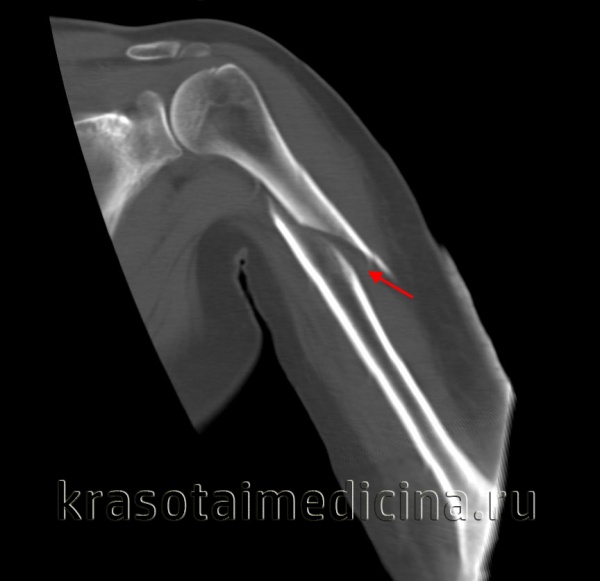

КТ плечевого сустава. Оскольчатый перелом хирургической шейки плечевой кости со смещением отломков. Дистальный отломок (красная стрелка) вколочен в проксимальный отломок (синяя стрелка).